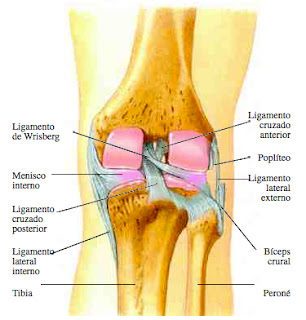

Lesión del ligamento

lateral externo

Descripción

El ligamento lateral externo (LLE) se encuentra fuera de la articulación

de la rodilla. Va desde la parte exterior del fémur hasta la parte exterior de la

tibia. Proporciona estabilidad a la rodilla y limita su movimiento de lado a

lado. La lesión del ligamento colateral externo es un desgarro parcial o

completo o un estiramiento excesivo del ligamento.